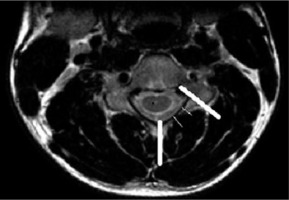

Figure 2

T2W axial image at the level of the pedicle in a normal person to show the method of determining the loss of attachment of posterior dura in the neutral position. The medial extent of lamina is at the level of the junction of 2 lamina and the lateral extent is the line along the medial side of the pedicle. This is divided into 3 equal parts to grade the degree of loss of dural attachment

Figure 3

T2W axial image at the level of the pedicle in a 16-year-old male with Hirayama disease, showing loss of attachment of the dura (arrow), which is more than one-third, as shown by lines dividing the lamina into 3 equal parts

LOA of posterior dura with anterior displacement was seen in all the patients (100%) on flexion MRI (Figure 7). LOA involved the whole of the posterior dura (bilateral) in 13 patients (76.4%) and only one side in 4 patients (23.5%). Maximum LOA was seen at the C6 level in 10 patients (58.8%), followed by C5-6 intervertebral disc level in 5 patients (29.4%), and C5 and C6-7 level in one patient each (5.8%). This LOA of the posterior dura was seen in 11 patients (64.7%) on neutral position MRI, as well (Figures 8 and 9). On evaluating axial T2W and T2 FFE images for LOA of posterior dura, mutual consensus was reached by 2 radiologists that it was better visualised on T2 FFE images (Figure 9). The mean thickness of this LOA on flexion was 3.7 ± 0.66 mm (mean ± 2SD).

Asymmetrical lower cervical cord atrophy is the most important imaging feature on neutral MRI that can suggest the diagnosis of HD. LOA can also be seen on neutral MRI. On evaluating neutral T2W axial images in our study, LOA was seen to be present in 64.7% of the patients. As per Chen et al. [13], LOA was the most effective finding in the diagnosis of HD in neutral position MRI, with sensitivity and specificity greater than 93.5%; however, Lehman et al. reported lower sensitivity (70%) of this finding [18].